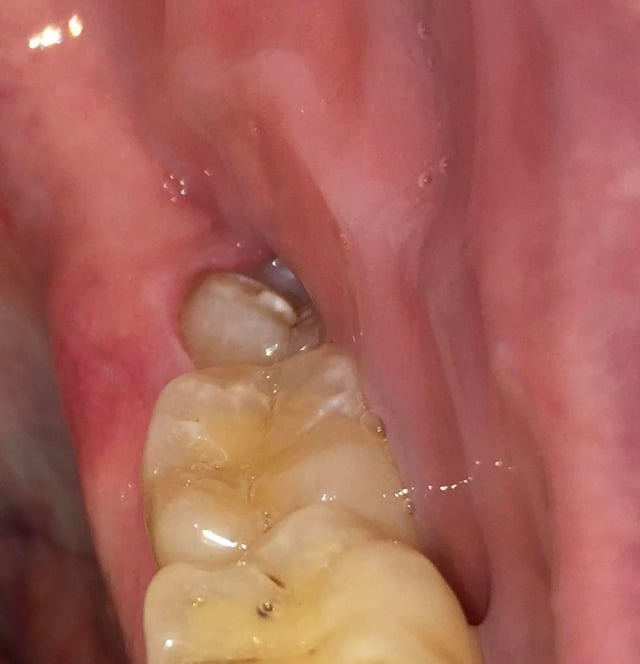

Heb al circa een week last van pericoronitis (wel vaker gehad). Deze keer duurt de genezing wat langer. Pijn is helemaal weg, maar het tandvlees daar is nog zacht en niet strak tegen de verstandskies. Foto 1 is hoe het nu is, zacht tandvlees, en foto 2 toen het gezond was waarbij het tandvlees strak is. Wanneer zal de zachtheid weggaan? Ik spoel al dagelijks met zoutwater. Ben ook van plan om in 2026 mijn verstandskiezen te verwijderen. Foto 3 en 4 zijn foto's van mijn verstandskiezen, heb alle 4 al meer dan 12 jaar niet laten trekken, maar denk dat ik het beter kan doen? Werd wel vaak gezegd tegen me dat het slim is om ze te laten trekken, maar ik ben altijd bang van zulke behandelingen.

JaxTeller

Ik had niet begrepen dat de foto's v uw tandvlees v April waren.. De tweede foto v uw verstandkies is de reden waarom ik de opmerking heb gemaakt.